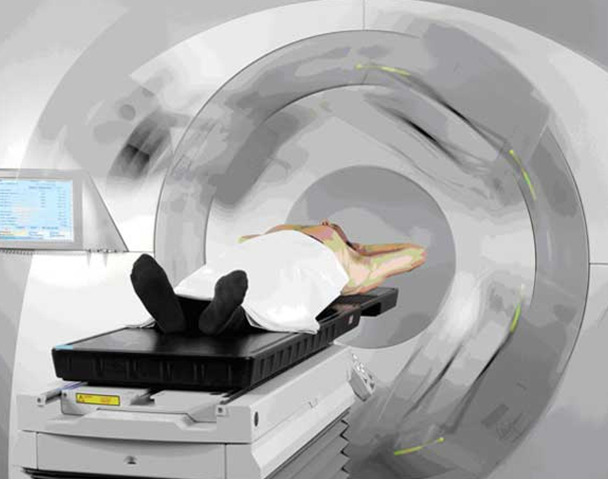

Radiation Oncologist with 7+ years of experience in Radiotherapy along with chemotherapy units. Experience in working with wide array of technologies, and expert with most advanced Linear Accelerator Radiation Modalities (Semiens, Varian Clinac ix, Elekta Versa HD, Novalis, Tomotherapy) and Eclipse version 10, Oncentra, MONACO treatment planning systems. Skilled in 3DCRT, IMRT, IGRT, RA/VMAT, SBRT & SRS.

Good experience with Cobalt and Linear Accelerator (3DCRT, IMRT, IGRT & VMAT).